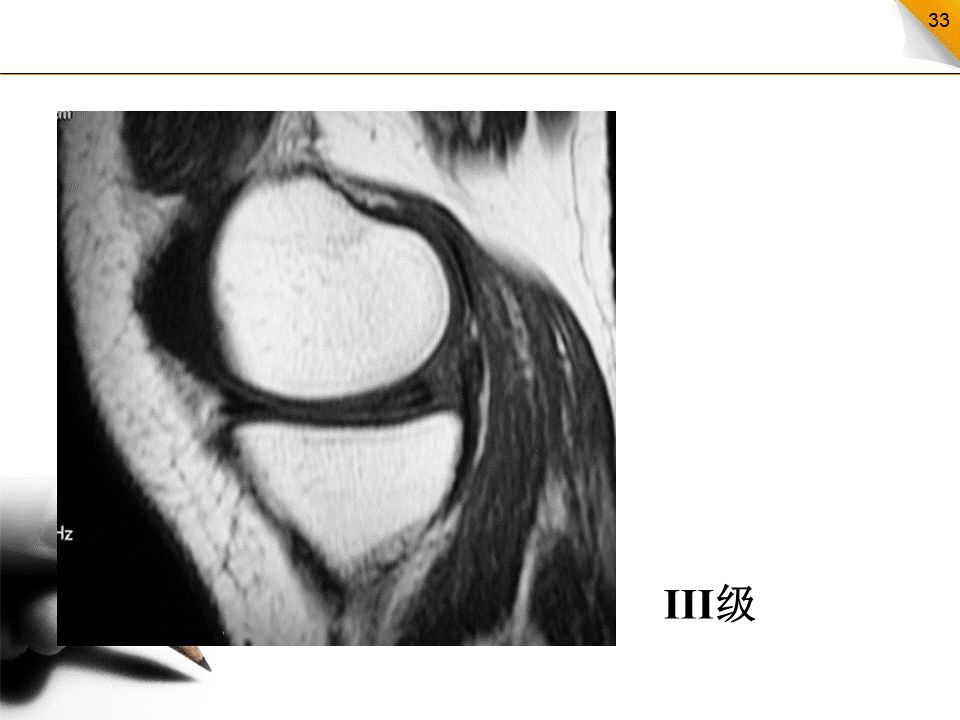

半月板损伤的MR分级

0级:正常半月板,均匀的低信号,形态规则I级:不与半月板关节面相接触的灶性信号增高影II级:半月板内线性信号增高,可延伸至半月板的关节囊缘,但未达到半月板的关节面缘,是I级信号改变的继续,范围更广III级:半月板内的高信号达到半月板的关节面,代表半月板的撕裂IV级:半月板破碎成多块并向关节腔内移位